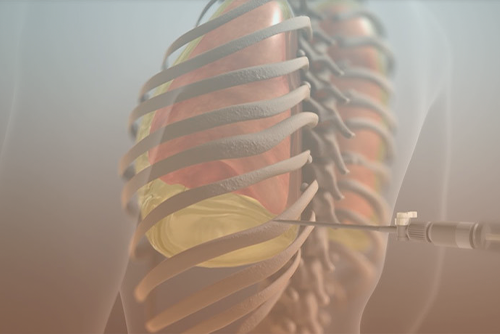

Диагностика плеврального выпота: что нужно знать